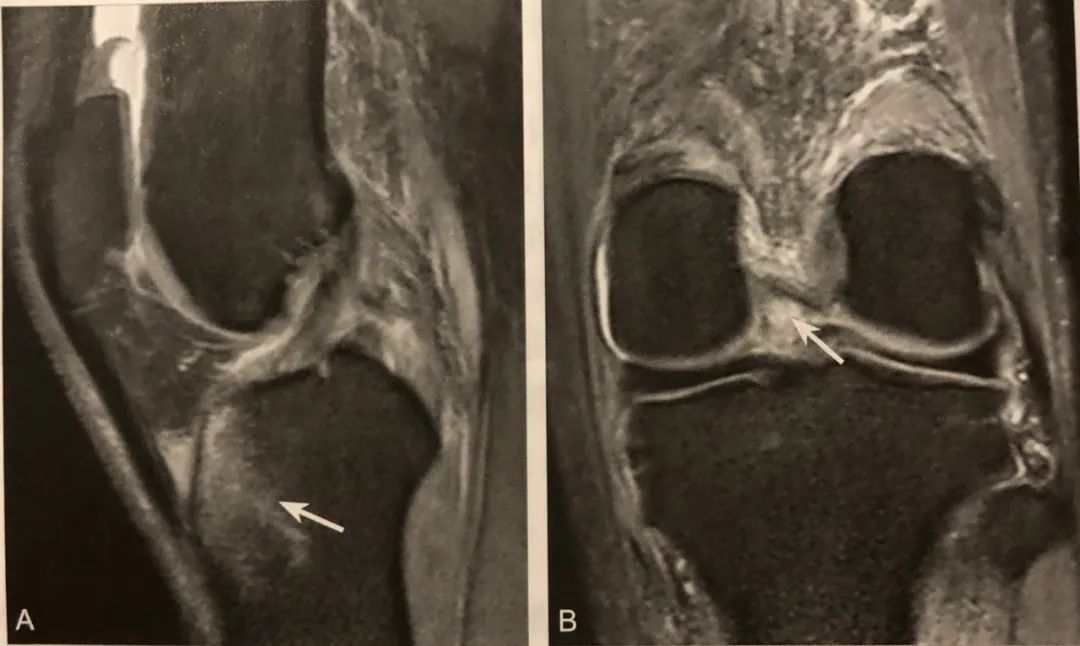

12骨挫傷および半月板損傷 膝痛の原因は様々ですが、膝関節内の半月板・軟骨・靱帯などの状態を調べるのに、MRI検査は非常に役立ちます。 この症例では脛骨の骨挫傷(→)と内側半月板後角損傷(*→)を認めます。 MRIトップ | 1乳腺疾患 | 2脳 骨挫傷の全治 骨挫傷の全治は、 無理に負担をかけなければ1カ月から3カ月前後 です。 ただ、もっと長引く場合もあります。 骨挫傷の部位や損傷の程度に異なるため、その症状次第になります。 骨挫傷の治療 骨挫傷の治療は、基本的に安静になります。 膝関節の痛み 軟骨の痛み(軟骨損傷と変形性膝関節症) 関節軟骨損傷 関節軟骨損傷は様々な原因により生じます。 加齢などにより徐々に軟骨の磨耗が進行するものと、外傷や繰り返す過度なストレ ス(スポーツ活動など)により生じるものに大別されます。

Vol13 骨挫傷 診断 レントゲンでは所見が見られなくても、mriで骨髄(骨の内部)に生じる異常信号像を骨挫傷と言います。mriのt1像で低信号(黒く)、stir像で高信号(白く)を呈しまず。ということは、 骨挫傷がある場合はその関節の靭帯がどこか切れていないか? と疑ってかかることが基本なんですね。 そして、靭帯が断裂していれば、そのせいで関節がぐらぐら状態となり、関節によっては脱臼を繰り返したり、また、脱臼までいかなくても、膝なら膝崩れが起こりやすかっ膝の骨挫傷単独例についての検討 本山 達男 , 川嶌 眞人 , 尾川 貴洋 , 田村 裕昭 , 古江 幸博 , 永芳 郁文 , 川嶌 眞之 , 佐々木 聡明 , 渡邊 裕介 , 小杉 健二 整形外科と災害外科 64(2), , 15